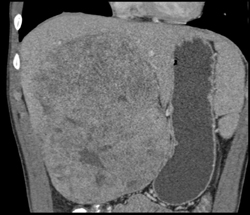

Hepatoma